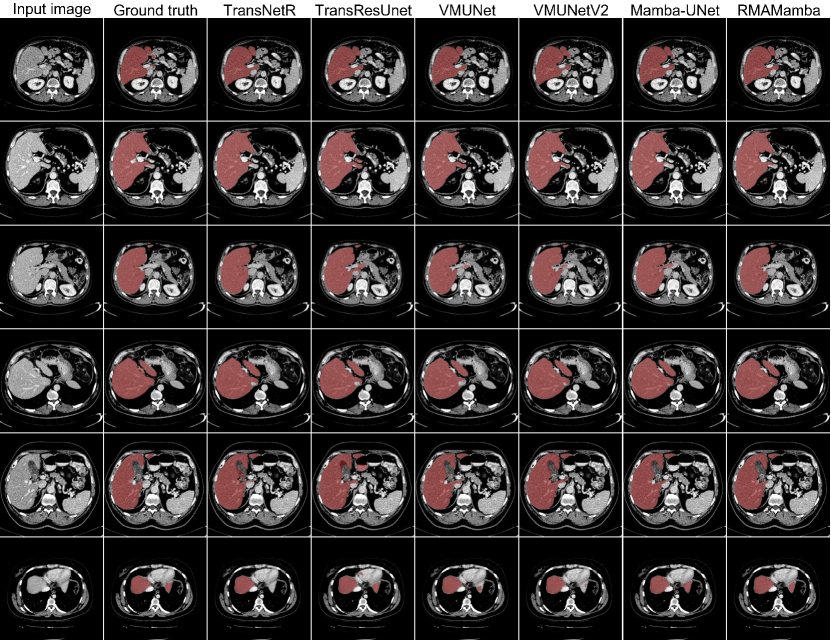

Refer to caption

Figure 3: Qualitative results of different methods on the LiTS dataset.

While Transformer-based methods (TransResUnet: 92.58%, PVTFormer: 92.48%) and CNN-based approaches (Double-UNet: 92.37%) demonstrate competitive performance, they incur substantial computational overhead and longer training times. RMA-Mamba achieves comparable or superior results while maintaining computational efficiency and faster training convergence. Qualitative analysis (Figure 2) further validates our method’s effectiveness, particularly in challenging cases. The visualization results, especially evident in rows three and five, demonstrate RMA-Mamba’s superior boundary delineation and enhanced discriminative capability at tissue interfaces.

Table 2 presents the quantitative results of various state-of-the-art models on the LiTS dataset. We can observe that RMA-Mamba-T achieves exceptional segmentation performance, with a Dice coefficient of 92.94%, mIoU of 88.99%, recall of 92.34%, precision of 95.59%, F2 score of 92.44%, and a HD score of 2.83 mm. RMA-Mamba-T achieved the highest Dice, surpassing PVTFormer by 0.46%, VM-UNetV2 by 0.89%, and ResUNet++ by 2%. Compared to RMA-Mamba-S, RMA-Mamba-T has fewer parameters yet delivers superior performance on the LiTS dataset. Additionally, RMA-Mamba-T offers faster inference speed and lower computational cost. Figure 3 shows that our model provides more accurate segmentation results than other benchmarked state of the art methods.